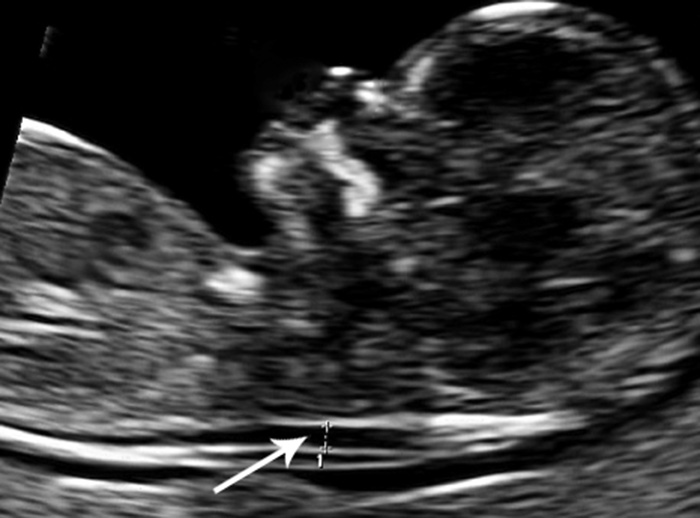

Ultralyd i uke 11 – 13 med måling av nakkeoppklaring (fig 1) og kombinert ultralyd og blodprøve (KUB-test) regnes som fosterdiagnostiske undersøkelser. Nakkeoppklaringen skyldes ødem i nakken hos fosteret, og blodprøvene som tas av mor og inngår i KUB-testen måler konsentrasjonen av humant choriongonadotropin (HCG) og svangerskapsrelatert plasmaprotein A (pregnancy-associated plasma protein A, PAPP-A). KUB-test predikerer sannsynligheten for kromosomavvik eller utviklingsavvik hos fosteret (4) – (6), og metoden ble innført for å unngå komplikasjoner knyttet til invasiv prøvetaking (7). Når ultralydundersøkelser utføres med mistanke om genetisk sykdom, skal det først gis genetisk veiledning. Ultralydundersøkelser i den alminnelige svangerskapsomsorgen, dvs. rutineundersøkelsen i andre trimester og undersøkelser på medisinske indikasjoner, anses ikke som fosterdiagnostikk og omfattes ikke av loven (1, 2).

Den fjerde kasuistikken tematiserer skillet mellom ultralyd som ledd i den alminnelige svangerskapsomsorgen og ultralyd som fosterdiagnostikk. Hvis det er mistanke om avvik ved en ultralydundersøkelse i den alminnelige svangerskapsomsorgen, bør kvinnen henvises videre. Økt nakkeoppklaring er den viktigste markøren for kromosomavvik, men måling av nakkeoppklaring er definert som en fosterdiagnostisk undersøkelse. Ut fra retningslinjene skal derfor henvisning videre basere seg på et inntrykk om at nakkeoppklaringen er økt, og ikke på en nøyaktig måling. 33 (52 %) privatpraktiserende gynekologer oppga likevel at de bare henviste videre dersom de selv hadde målt at nakkeoppklaringen var økt. Skillet mellom undersøkelser på medisinsk indikasjon og fosterdiagnostikk praktiseres ikke konsekvent. Én årsak kan være usikkerhet blant norske leger for om de bryter loven dersom de måler fosterets nakkeoppklaring.